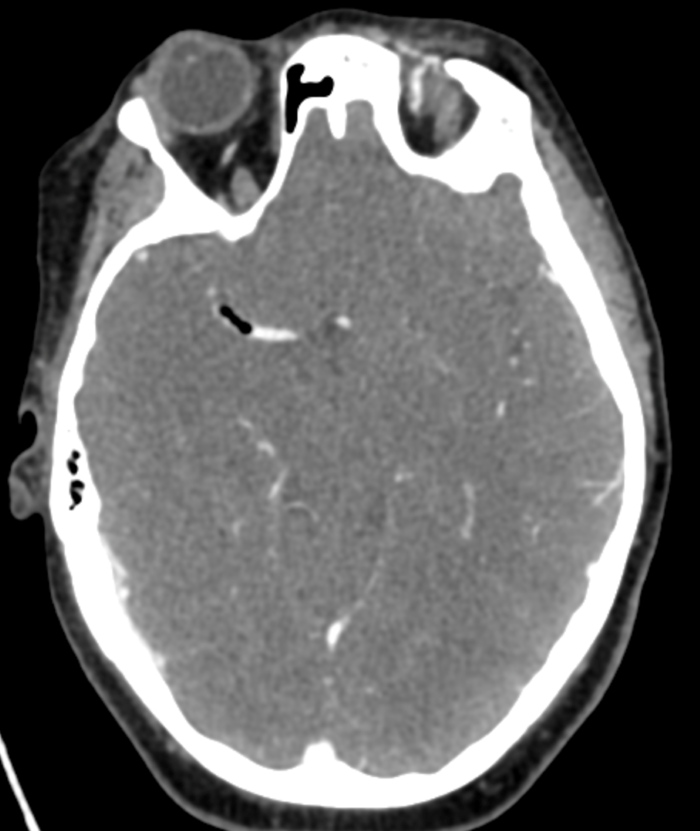

Initial objective data included T 37C, HR 85, RR 20, BP 153/109, spO2 98%. Glucose 102. Basic labs obtained and were unremarkable. Patient was rapidly taken to CT for stroke imaging. No contraindications to thrombolytics were identified. At 1708, noncontrast head CT showed no hemorrhage, but an abnormal hypodensity along the right middle cerebral artery concerning for an air embolus was visualized. CT angiogram head and neck was also suggestive of air embolus and CT perfusion brain demonstrated 27 mL of critical hypoperfusion at the right posterior middle cerebral artery distribution.

Figure 1: Non contrast Head CT showing air in the R MCA distribution